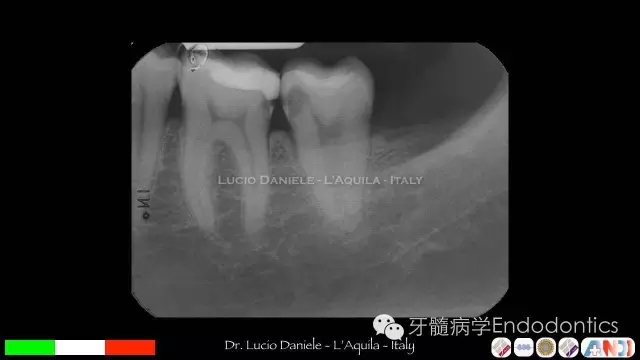

圖9.